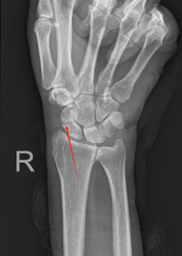

术前X片显示骨折处        术后X片显示螺钉位置良好

舟骨骨折与股骨颈骨折、小腿中下三分之一部位的骨折,通称为人体三大比较难愈合的骨折部位。对于骨折端异位的患者,必须通过对齐骨折线创造骨折愈合条件,否则容易导致舟骨骨折断端不愈合,甚至出现舟骨坏死的情况。机器人辅助的经皮舟骨螺钉内固定能在极小的创伤下,帮助舟骨骨折端精准地对齐和固定,避免保守治疗不愈合的风险和常规手术创伤的危害,达到较好的治疗效果。